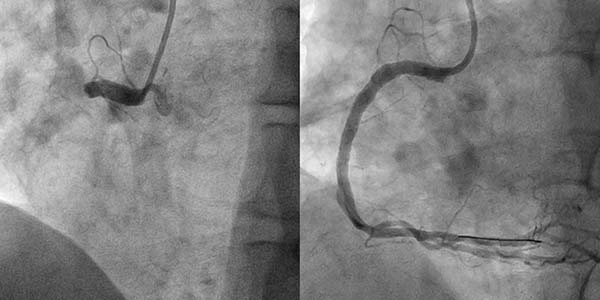

案例1

张先生2025年4月28日因劳累时胸闷就诊于清华大学附属垂杨柳医院心内科,入院后拟择期完善冠脉造影检查评估冠脉。然而术前检查中血常规项目中的轻度贫血及便潜血阳性引起了管床医生的警惕。消化内科会诊认为患者贫血原因需考虑消化道出血导致可能,因患者存在抗血小板类药物使用相对禁忌,遂决定暂停抗血小板类药物使用,为消化内科内镜检查做准备,同时放弃冠脉造影检查并改为完善冠脉CTA检查初步评估冠脉。然而检查结果却不容乐观,冠脉CTA提示张先生冠状动脉多发中-重度狭窄。消化内科与心内科共同评估病情后决定先行胃镜检查,病理结果显示低分化腺癌。需要限期手术,但是合并冠状动脉严重狭窄外科围术期发生急性心血管事件风险极高。而冠心病治疗需使用抗血小板类药物,冠脉介入治疗术中需使用抗凝药,患者消化道出血风险也很高。心内科团队及普外科团队经共同讨论后制定了治疗方案:先由心内科处理冠脉病变,之后由普外科尽早完成切除胃部肿瘤。冠脉造影结果显示:右冠脉严重狭窄。考虑到患者需要尽快接受外科手术,心内科冠脉介入团队讨论后决定应用新型药物涂层支架干预右冠脉(可减少术后双联抗血小板时间至最少1个月)。经1个月双联抗血小板治疗后,经麻醉科、心内科、普外科再次评估后,于2025年6月24日由普外科完成腹腔镜下肿瘤切除术。